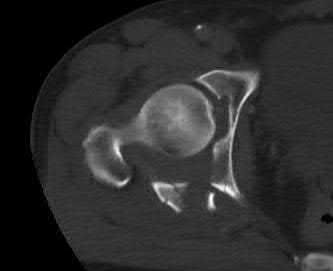

A 15-year-old boy presents with a permeative lytic lesion in the femoral diaphysis with aggressive periosteal reaction ('onion skinning'). Biopsy reveals uniform small round blue cells. Cytogenetic analysis of this tumor will most likely demonstrate which of the following translocations?

Explanation

The clinical and radiographic description is classic for Ewing sarcoma. The characteristic cytogenetic abnormality is a balanced translocation t(11;22)(q24;q12), which fuses the EWS gene on chromosome 22 with the FLI1 gene on chromosome 11. This is seen in approximately 85-90% of Ewing sarcomas. t(9;22) is the Philadelphia chromosome (CML), t(X;18) is seen in synovial sarcoma, t(2;13) in alveolar rhabdomyosarcoma, and t(12;16) in myxoid liposarcoma.